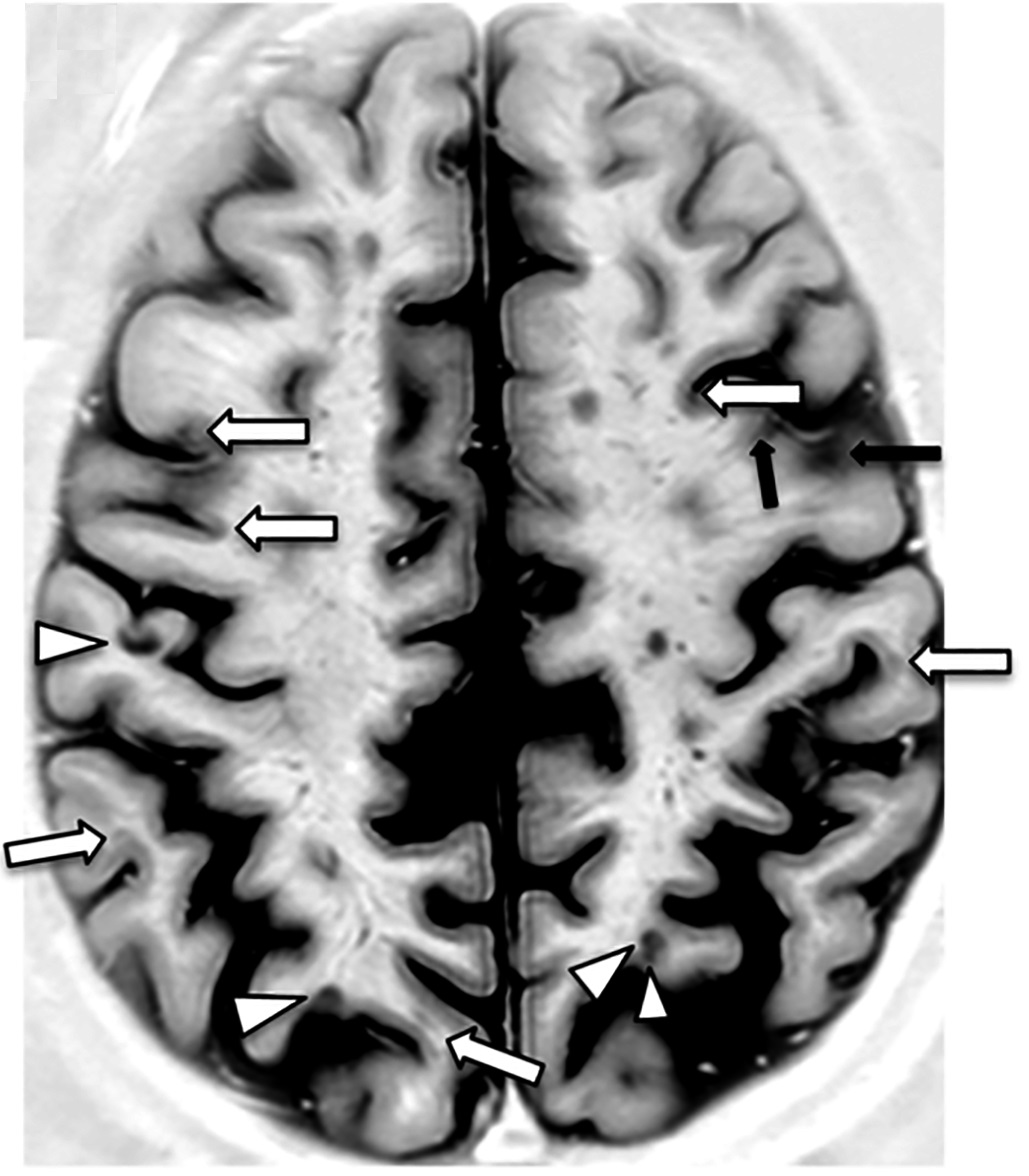

Axial PSIR MRI of a brain with multiple sclerosis lesions, Wikimedia Commons

- 측뇌실 주위 (periventricular white matter)